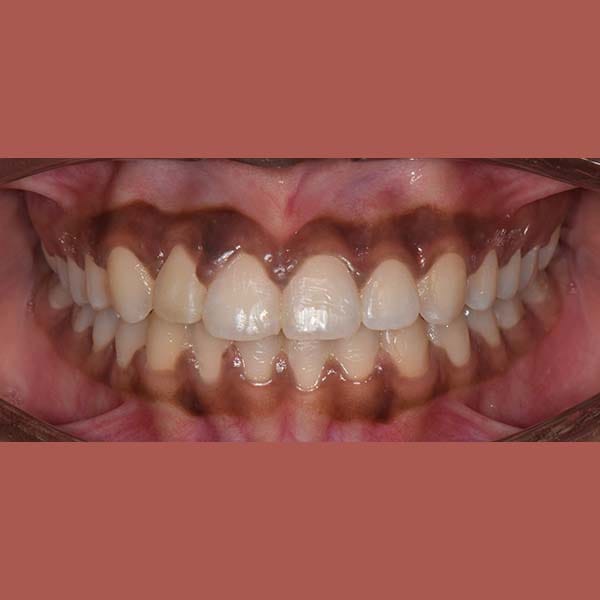

AFTER